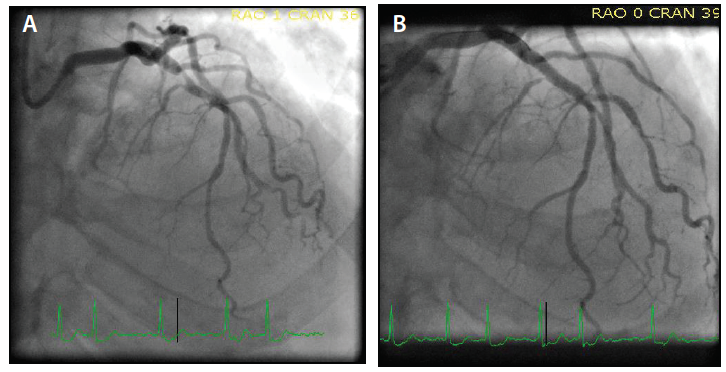

An extra backup (EBU) 3.5 Launcher® guide catheter (Medtronic) was preloaded with the 0.035-inch Railway™ dilator (Figure 5A) to match the 100-cm marker. The JR 4 guide catheter was pulled back over a 0.035-inch J wire secured in the ascending aorta. The assembly of the Railway™ dilator and EBU guide catheter was inserted (Figure 5B) up the right brachiocephalic artery. The dilator was removed, and using a 0.035-inch wire and standard practices, the left main artery was cannulated. The first obtuse marginal artery 90% stenosis (Figure 6A) was successfully treated with the same 1.5-mm balloon and a 2.75- X 15-mm Cobra PzF™ stent, with a very good angiographic result (Figure 6B). Subsequently, the left anterior descending (LAD) lesion (Figure 7A) was successfully treated using a 3.5- X 15-mm Cobra PzF™ stent, which was postdilated with a 4-mm noncompliant balloon showing a very good angiographic result (Figure 7B). After completing final orthogonal angiography, the guide catheter was removed over a 0.035-inch wire to the right RA and a TRAcelet™ compression device (Medtronic) (Figure 8A) was applied.